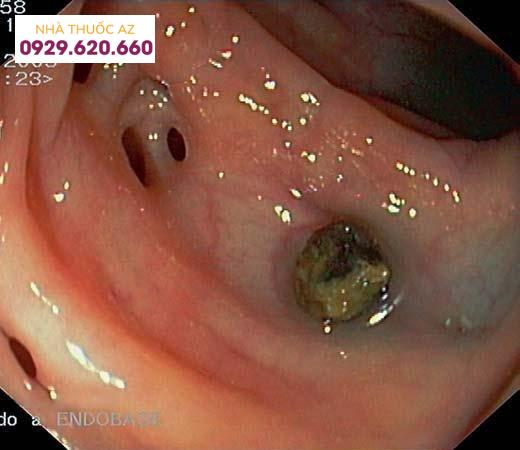

4. Nội soi đại tràng

Túi thừa ĐT với hình ảnh sỏi phân bên trong

Túi thừa ĐT viêm: sung huyết niêm mạc lòng ĐT và mủ ở cổ túi thừa (Nguồn: Parra-Blanco (2006), “Colonic diverticular disease: pathophysiology and clinical picture”, Digestion, Vol.73 Suppl 1 47-57)

Hình ảnh nội soi đại tràng cho thấy đại tràng có nhiều túi thừa

Nội soi đại tràng rất có ích trong chẩn đoán bệnh túi thừa đại tràng không triệu chứng và là một phương tiện điều trị hữu hiệu trong chảy máu túi thừa ĐT. Tuy nhiên, trong VTTĐT, nội soi ĐT được xem là chống chỉ định tương đối vì quá trình bơm hơi làm tăng áp lực trong lòng ĐT và có thể làm vỡ túi thừa đang viêm cấp gây biến chứng VPM.

Mặt khác, tương tự như chụp ĐT, nội soi ống mềm chỉ khảo sát được bên trong lòng ĐT, trong khi biểu hiện của VTTĐT chủ yếu xảy ra ở phía bên ngoài lòng ống tiêu hóa, nên nội soi cũng không cung cấp nhiều thông tin cho chẩn đoán VTTĐT. Tuy nhiên, nội soi ĐT có vai trò theo dõi những bệnh tăng sinh sau khi điều trị VTTĐT.